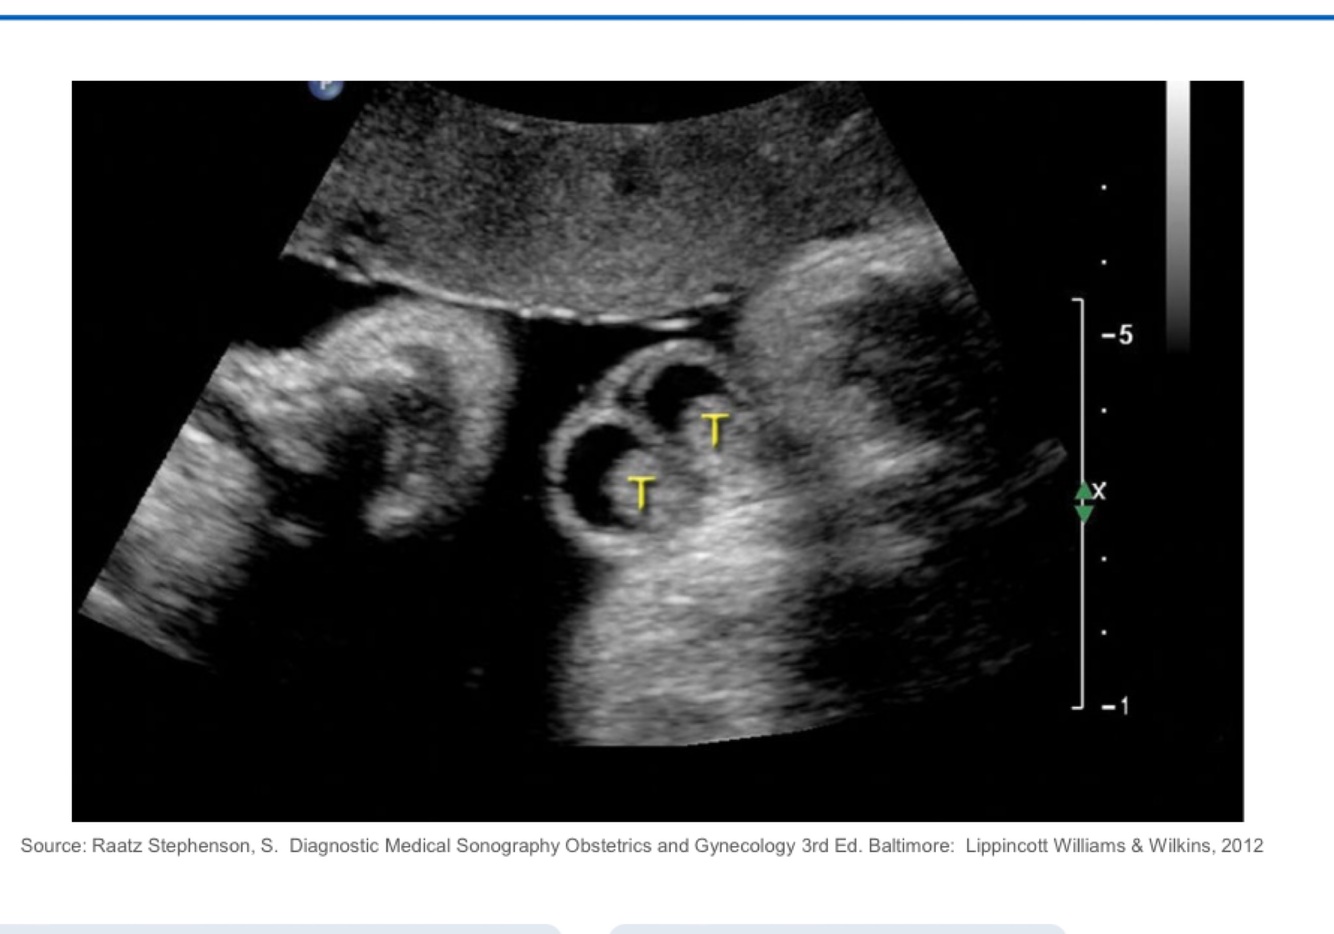

What does this image demonstrate?

Fetal hydrops two body